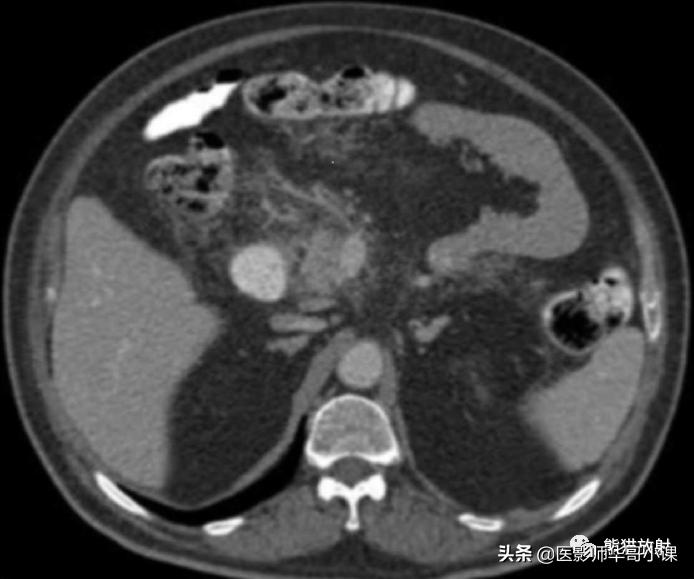

6、惠普尔病 Whipple’s Disease

是一种罕见的由革兰阳性杆菌引起的多系统受累的感染性疾病。CT可见小肠壁弥漫性增厚,肠系膜及腹膜后多发肿大淋巴结, 淋巴结密度较低 ,这是由于脂肪和脂肪酸的沉积造成的(图)。

惠普尔病。小肠系膜内可见无强化的低密度淋巴结(箭)